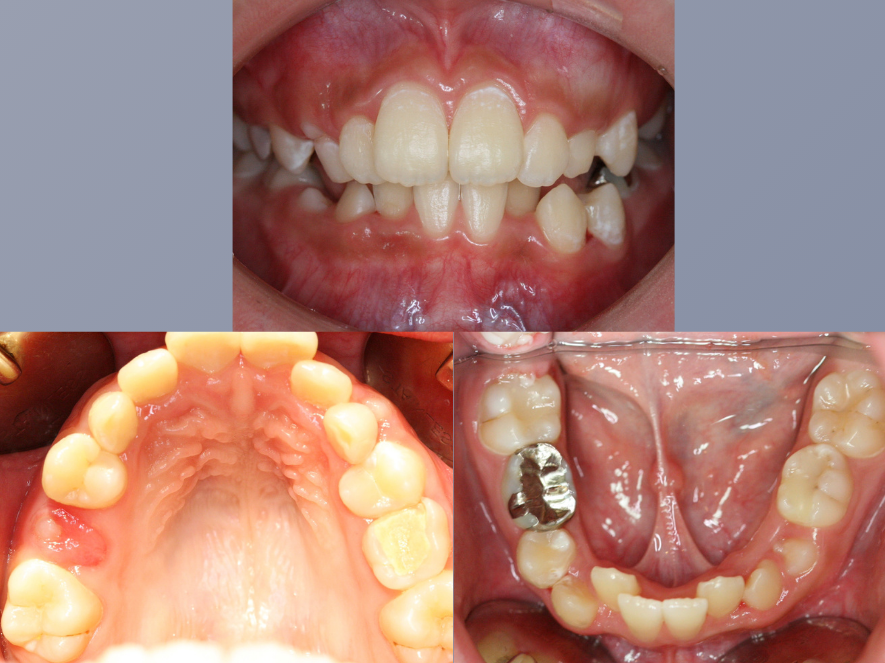

治療前

治療後

| 年齢・性別 | 10代・女性 |

| 主訴 | 生えてきた永久歯の歯並びが気になる |

| 期間 | 3年4ヶ月 |

| 費用 | 1,001,000円(税込) |

| 治療内容 | 矯正の前半に舌側から付ける装置で、歯の裏側に装着するため他人からは全く見えません。 顎の位置を正常な位置にもっていくという一番大切な治療を平行して行い、舌房や気道を広げます。 歯並びだけではなく健康な口腔内を作り出していくことが可能です。 |